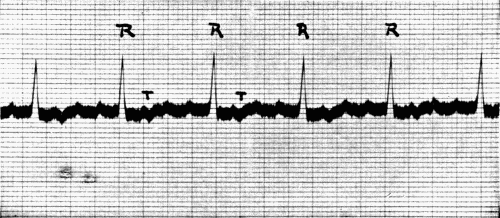

39. Normal electrocardiogram128

40. Auricular flutter132